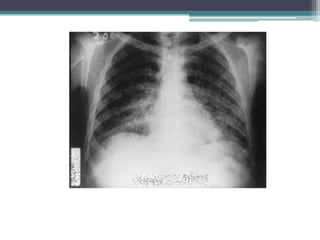

• La radiografia de torax muestra infiltrados

apicales fibrosonodulares uni o bilaterales.

• 1/3 permanece estable o mejora el resto empeora

apareciendo retracciones o cavitaciones en los

lóbulos superiores.

• La radiografiade torax muestra infiltrados apicales fibrosonodulares uni o bilaterales. • 1/3 permanece estable o mejora el resto empeora apareciendo retracciones o cavitaciones en los lóbulos superiores. • La aparición de enfisema o bullas compromete la función respiratoria.